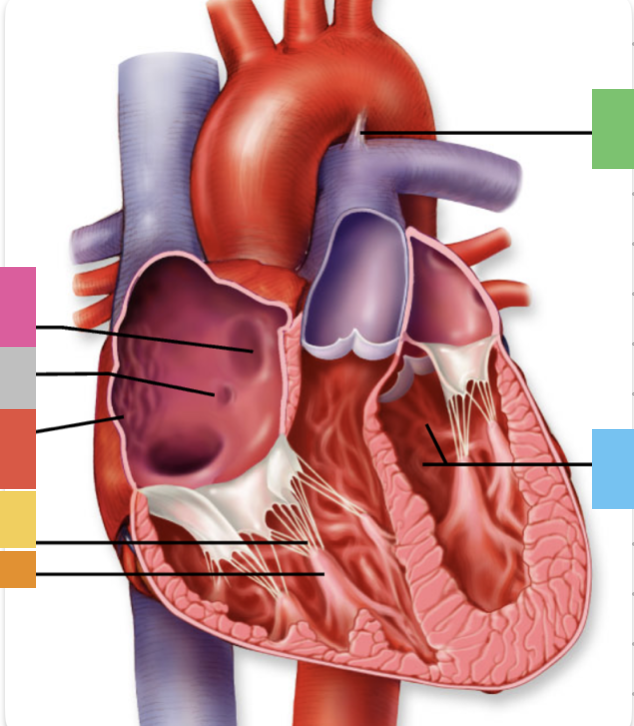

light purple

base

purple

apex

grey

right atrium

pink

right auricle

green

left atrium

green

left auricle

blue

right ventricle

orange

left ventricle

green

coronary (atrioventricular) sulcus

pink

interatrial septum

dark blue

interventricular septum

green

anterior interventricular sulcus

green

posterior interventricular sulcus

orange

aortic valve

yellow

pulmonary valve

red

tricuspid valve (right AV)

purple

bicuspid valve (left AV)

yellow

chordae tendineae

orange

papillary m.

blue

trabeculae carneae - only in ventricles

red

pectinate m. - only in R atrium

pink

fossa ovalis

grey

opening of coronary sinus